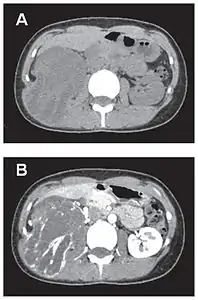

En tomodensitométrie[20],[31], quelle que soit la localisation, une tumeur fibreuse solitaire apparaît comme une masse tissulaire ovoïde ou lobulée, bien délimitée, refoulant les structures voisines sans les envahir. Elle se rehausse fortement après injection de produit de contraste. Les tumeurs de petite taille sont homogènes, mais les plus volumineuses présentent des plages hétérogènes de nécrose et d'hémorragie intra-tumorale. Il n'y a pas habituellement de calcifications et, lorsqu'elles sont présentes, elles sont de petite taille[31]. Les tumeurs malignes peuvent se présenter accompagnées de nodules pulmonaires métastatiques, et tendent à être plus volumineuses et plus hétérogènes[42].

- Tumeur fibreuse solitaire du rétropéritoine

Aspect tomodensitométrique, sans (A) puis avec (B) injection de produit de contraste[44].